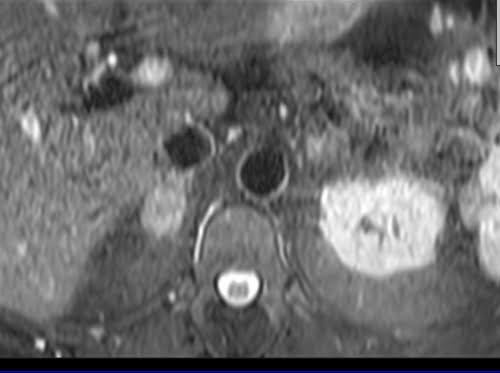

Adrenal MRI T2 TSE fat sat axial images